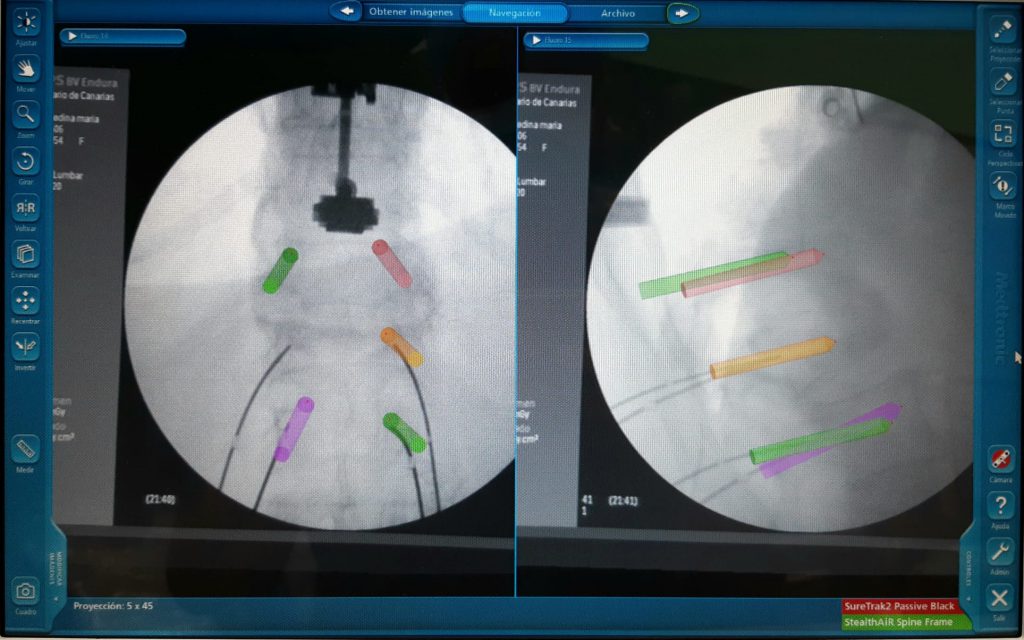

El servicio de Neurocirugía de este centro hospitalario utiliza habitualmente elnavegador en cirugía craneal y ahora ha incorporado esta tecnología en cirugía de columna, lo que permite una precisión milimétrica en la colocación de los implantes, menor tiempo de intervención y disminución en la dosis de radiación intraoperatoria.

El Dr. Héctor Roldán, neurocirujano del centro hospitalario, destaca “la mayor precisión y rapidez.” Señala también que el servicio de Neurociguría del HUC tiene gran experiencia en cirugías minimamente invasivas y “la incorporación de este navegador supone incrementar las posibilidades de desarrollo de las mismas.”

Destacar también la importancia del navegador como instrumento educacional. La correlación constante entre la localización del instrumento quirúrgico y el lugar del campo operatorio, acelera las curvas de aprendizaje. La utilización de pantallas indica a todos los profesionales que participan en el quirófano de la situación y la etapa en la que se encuentra la cirugía con lo que se sienten más involucrados en el acto quirúrgico.